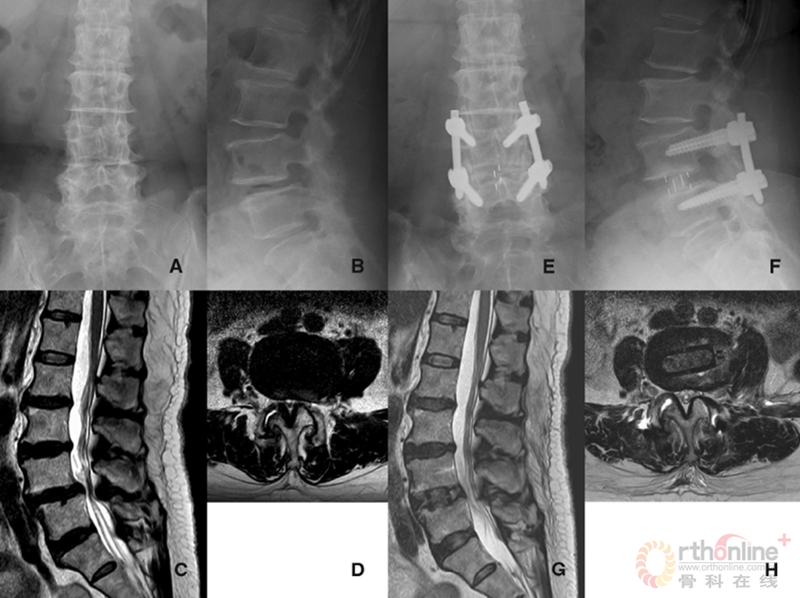

在微创脊柱外科热潮汹涌而至的当下,腰椎退变性疾病的治疗快要达到“无微不至”的程度。那么,就脊柱领域难度超高、风险性巨大的退变性脊柱侧凸而言,医生如何选择开放或微创技术,成为目前脊柱外科的热点之一。

陆军总医院、全军骨科研究所李放教授分析了国内外相关研究,并结合临床经验得出结论:开放手术能够获得更好的矫形和减压效果;微创技术作为脊柱医生手中的新武器,对于一部分畸形较轻的病例,微创技术可以发挥其优势,但要严防特殊并发症;对于畸形严重的病例,微创手术处理存在困难,可谓开放能及微创所不及。他认为,开放和微创技术应该有机结合,重要的是如何去选择适应证,对不同的病例制订个体化方案。